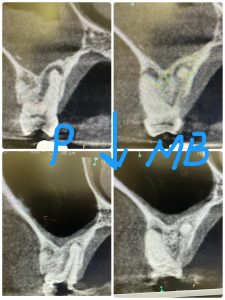

根管治療開始3ヶ月、本日根充

MB根は全く開かないが、細管通じて病巣は縮小傾向

洞内粘膜肥厚もほぼ消失

また来年CT撮影し経過みる